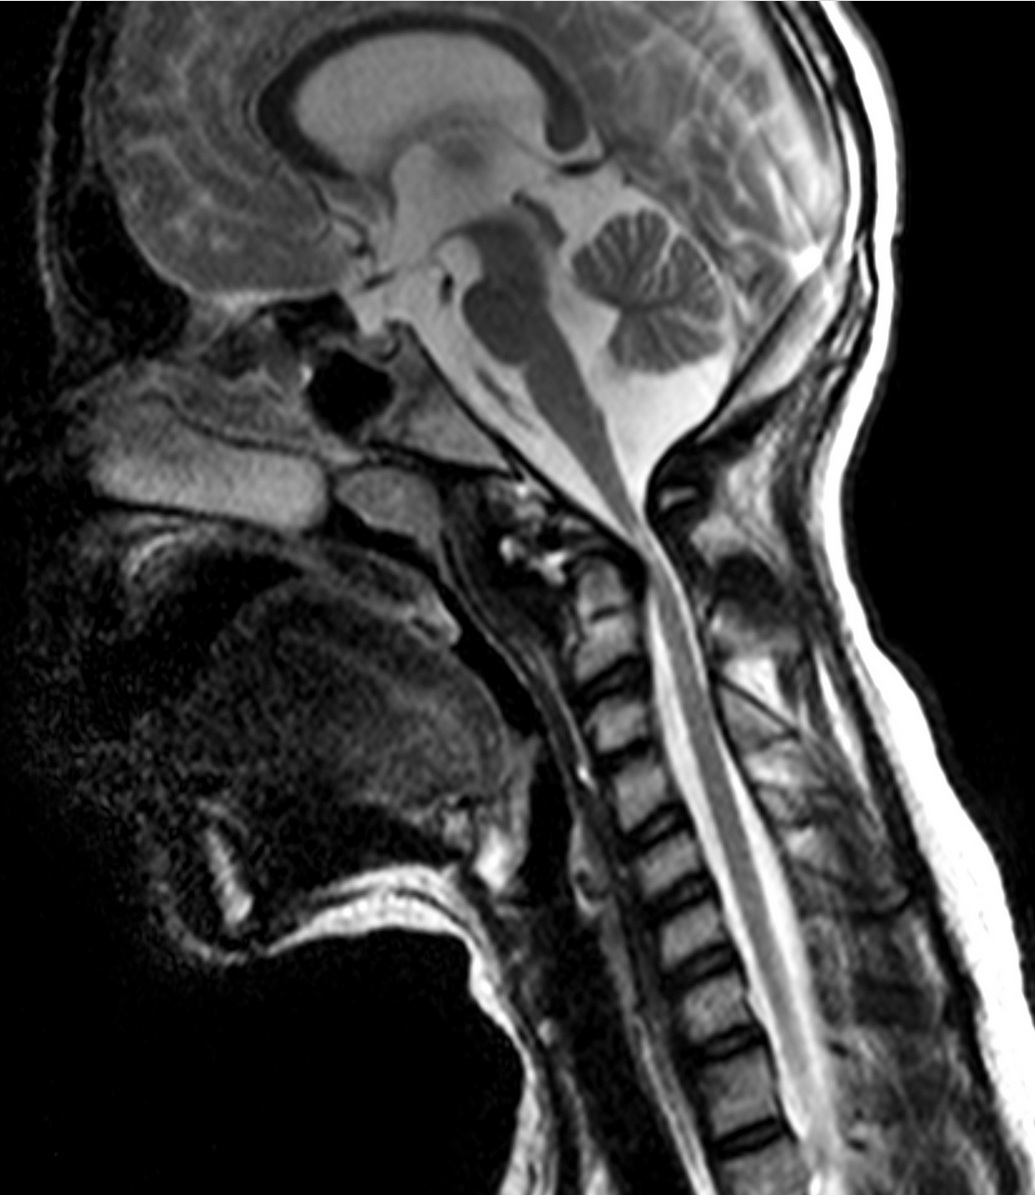

Evaluación de compresión cervicomedular y decisión de descompresión posterior.

Correlación clínico-radiológica y decisión de descompresión según síntomas y hallazgos.